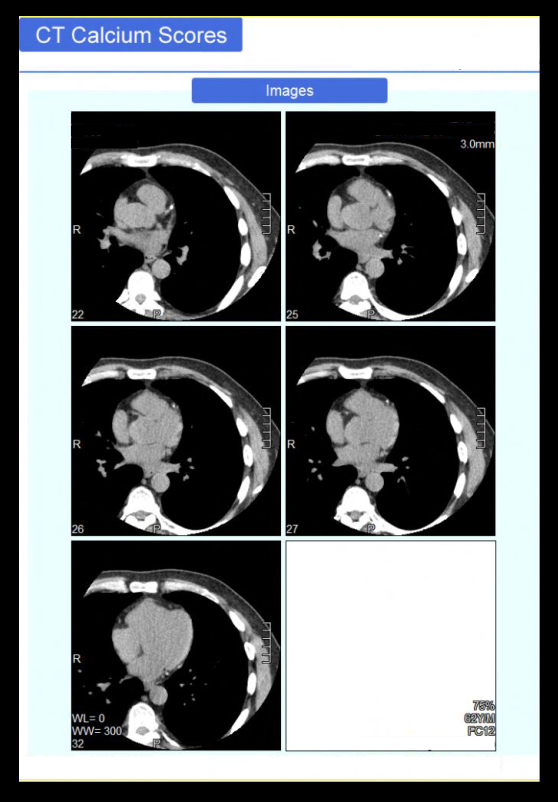

- Axial images in cardiac window (WW: 1000, WL: 400) with 3mm slice thickness.

- Calcium score analysis report.